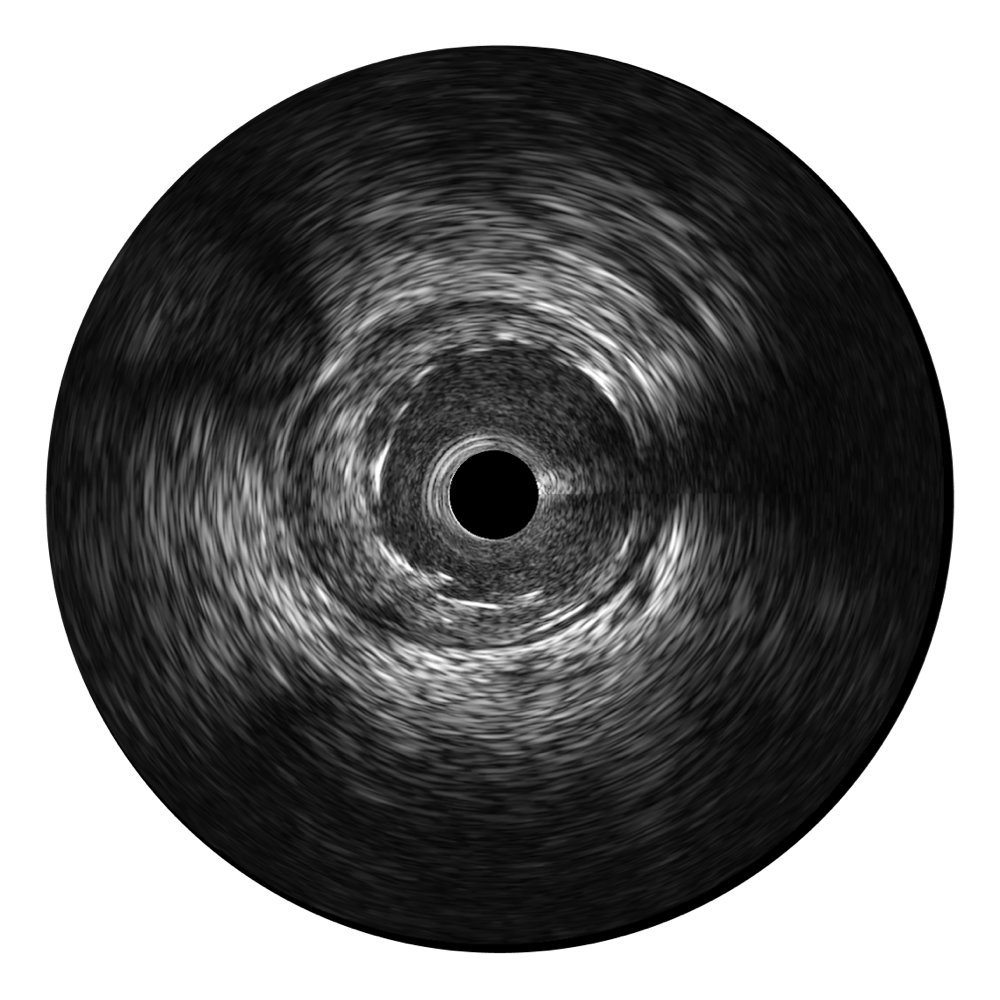

db真人体育官网宽频IVUS图像

对比传统IVUS导管成像,db真人体育官网宽频IVUS图像的近场支架梁显影更细腻,远场中膜外血管仍清晰可辨,兼顾远中近,兼顾分辨力与穿透深度